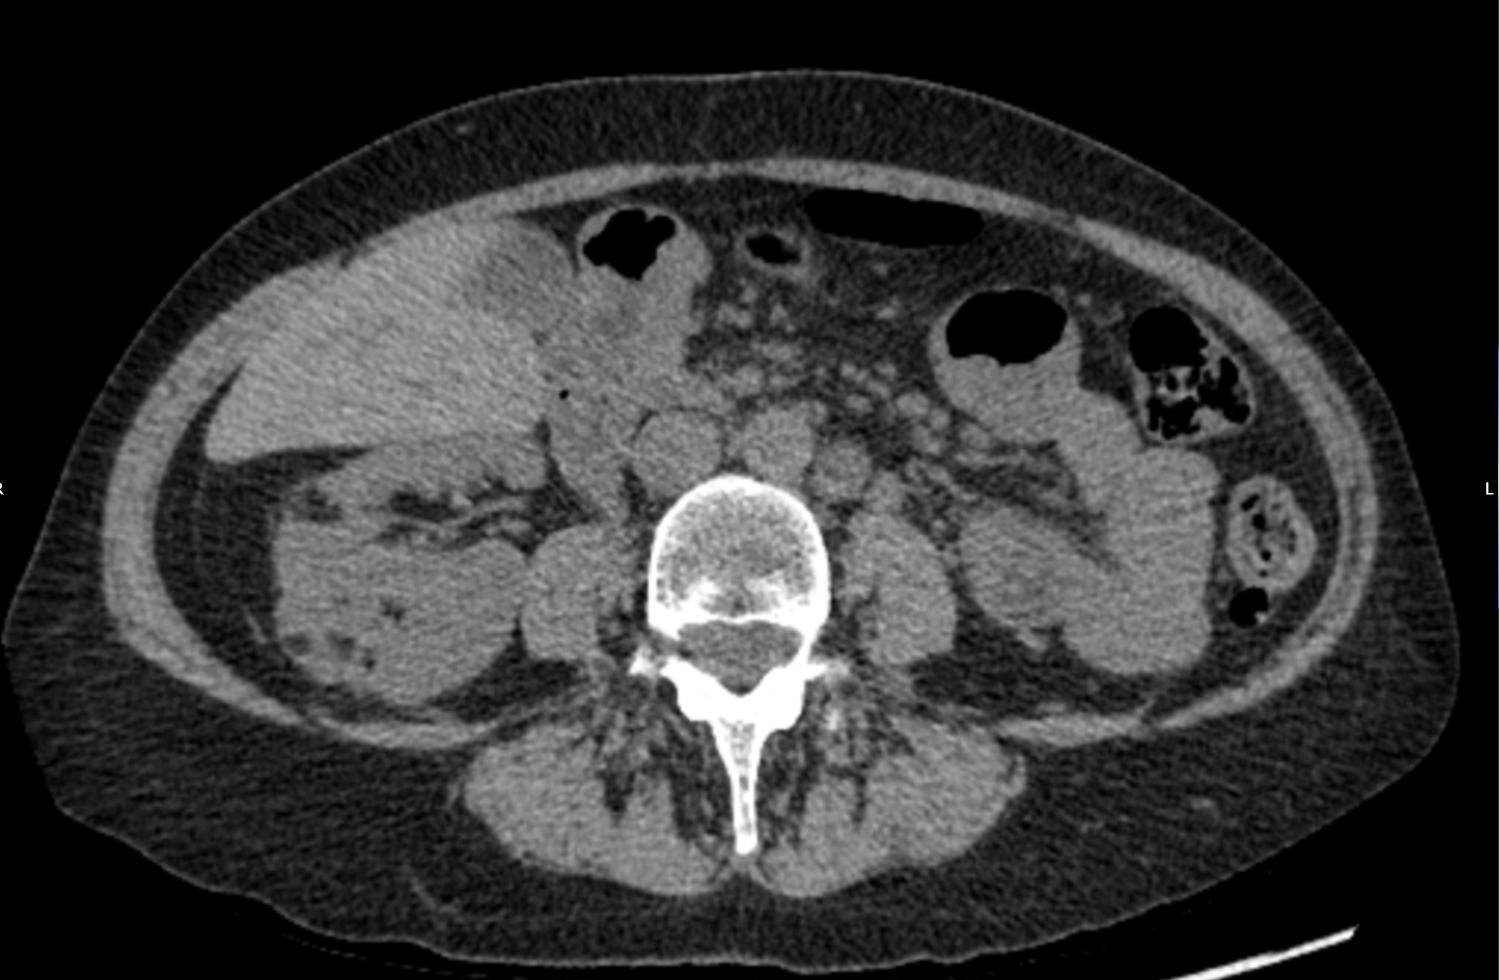

A 45 year old female patient was referred by her GP for a renal ultrasound to investigate hypertension resistant to drug treatment. She was otherwise in good health and had no previous medical history of note or relevant family history. Representative ultrasound images of the kidneys are shown in Figures 1 and 2.